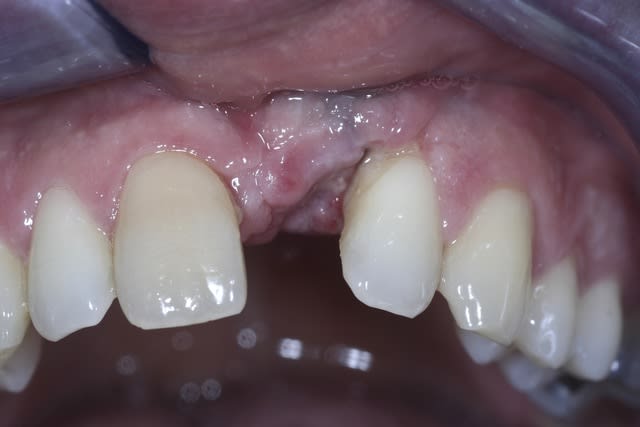

Exact, l'implant y est déjà ; avec une belle inclinaison mésio-distale.

Je ne gère "que" la partie prothétique, et c'est plutôt le côté mésial de 22 qui me pose problème.

l'implant à l'air très vestibulé aussi, on le distingue par transparence. as-tu une rétro stp?

le problème, est multiple ici...réduction de l'espace MD, position de l'implant, défaut osseux, gencive pas si géniale (malgré ton intervention)...çà va pas être très simple à gérer...

La teinte est due à un tatouage de la gencive, j'ai bien atténué lors de la chir mais toujours visible.

Oui, qq spires sont apparentes au travers de l'os.

Je me bile pas, le patient est prévenu ; il a un partiel 1 dent depuis plus de 3 ans, je pense que la couronne lui changera radicalement les choses mais j'aimerais éviter la céram rose en mésial de 22.

Mais reconstruire des papilles je sais pas faire.